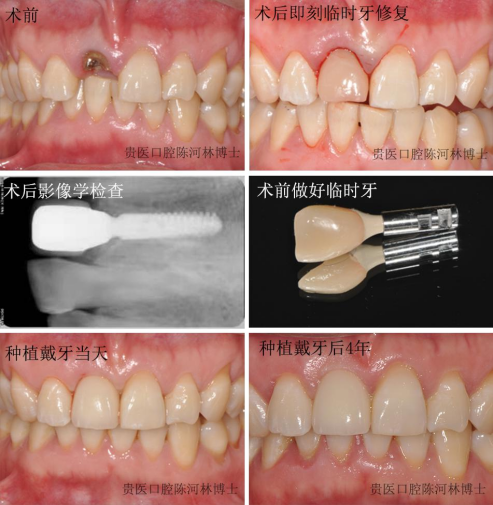

门诊接诊了一名年轻女性患者,该患者因车祸致上前牙折断,影响美观,来门诊要求镶种植牙。完善术前检查后,给予患者即刻种植+即刻修复治疗,第一时间改善了患者缺牙影响美观的问题。临时修复后半年,给患者戴上最终修复体,患者非常满意,自觉完全看不出这是假牙。

术后4年复查,种植牙周围牙龈形态较刚戴牙时更协调。临床上经常会遇到因外伤致上前牙折断或者缺失的患者,通过合理的诊断设计,术前检查完善的前提下,即刻种植+即刻修复治疗方案能解决美观问题,而且远期效果也非常好。